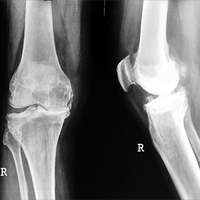

Case:1 TKR

Pre-Op Lateral

Pre-Op AP